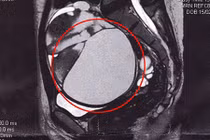

Sau khi thăm khám và làm các xét nghiệm cận lâm sàng, Bác sỹ chẩn đoán bệnh nhân đã bị vòng tránh thai lạc vào bàng quang, dần dần hình thành sỏi bàng quang, kích thước (5x6)cm.

| Hình ảnh vòng tránh thai đi lạc tạo sỏi trong bàng quang - Ảnh: BVCC |

Th.S BS. Ma Ngọc Ba - Trưởng khoa Ngoại Thận - Tiết niệu cho biết: “Bệnh nhân đã được áp dụng phương pháp tán sỏi bàng quang ngược dòng bằng laser hiện đại. Sỏi được tán vụn bằng laser, sau đó vòng tránh thai được ra khỏi cơ thể mà không phải mổ mở, bệnh nhân hồi phục sức khỏe sớm, thời gian nằm viện ngắn”.